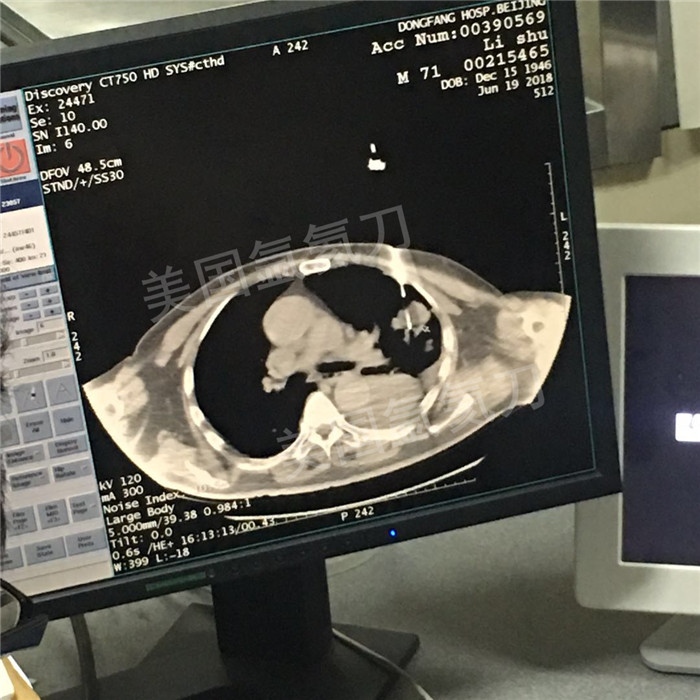

上一篇:唐山市人民医院氩氦刀冷冻消融治疗肺癌

下一篇:平度中医院右肺上叶肿瘤氩氦刀冷冻消融治疗